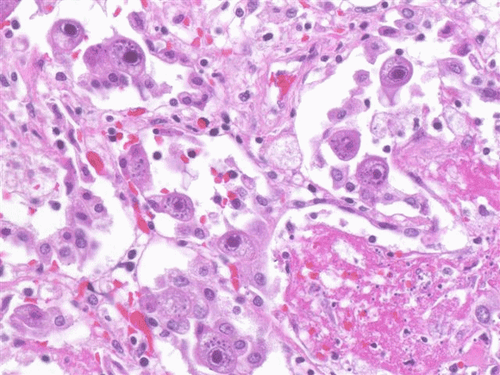

7. Sinh thiết phổi, hình ảnh giải phẫu bệnh

Cần thiết để chẩn đoán xác định viêm phổi do cytomegalovirus.

Hình ảnh giải phẫu bệnh tổn thương phổi có các tế bào phế nang khổng lồ với hình ảnh hạt vùi bào tương và hạt vùi CMV trong nhân với vòng sáng quanh nhân tạo ra hình ảnh giống mắt cú cùng với xét nghiệm PCR CMV dương tính là tiêu chuẩn vàng để chẩn đoán viêm phổi do CMV.

Sinh thiết tế bào phổi tổn thương do nhiễm CMV